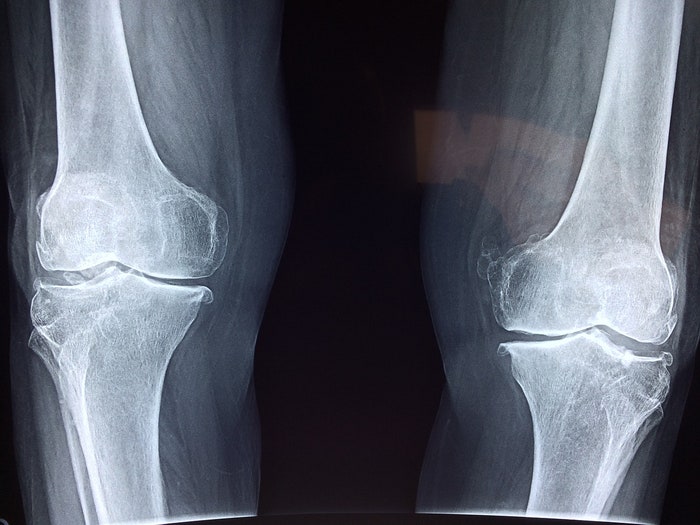

간단하고 필수적인 건강관리법 무릎연골수술 정보

무릎 연골 수술에 대한 보충 권장 사항 및 유용한 정보

발생할 수 있는 문제에 주의를 기울이지 않는 무릎 연골 수술 정보 공유 다음으로 건강에 주의를 기울이지 않아 발생할 수 있는 피해에 대해 이야기해 보겠습니다. 먼저 폐암, 췌장암, 유방암 등 잘 알려진 질환의 경우 확률이 41.32% 내외로 꾸준히 증가하고 있으니 주의해야 한다. 초기에 눈치채지 못하면 평균 치료주기는 9년, 1회당 130만원의 비용이 발생하는데, 항암치료를 계속 받으면 후유증이 생길 수 있다. 또한 질병을 같은 방법으로 예방하지 않으면 치료 과정에서 2주마다 거액의 돈이 터지고, 시간이 길수록 비용 자체가 커지므로 전공 전에 질병을 조심해야 한다. 수술. 지금 바꾸면 효율적으로 관리할 수 있습니다. 무릎연골수술을 찾으시는 분들은 현대의학이 많이 발전하고 평균수명이 늘어났다고 하지만 그렇다고 건강관리를 무시할 수 있는 것은 아닙니다. 위에서 언급한 바와 같이 건강한 몸을 만들기 위해서는 꼼꼼한 건강관리와 주 3회 이상의 운동으로 몸을 보호해야 합니다. 요즘 많은 보충제가 판매되고 있기 때문에 필수 영양소의 약 40%를 유지하는 것이 많은 도움이 됩니다.이전 이미지 다음 이미지